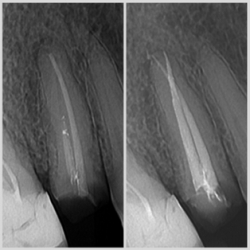

Endodontski zahvat predstavlja liječenje korijenskih kanala zuba s ciljem očuvanja zuba u usnoj šupljini. Postupak podrazumijeva vađenje, odstranjivanje pulpe zuba iz kanala, čišćenje i ispiranje korijenskih kanala posebnim ručnim ili strojnim iglicama i tekućinama za ispiranje koje odstranjuju zaostale bakterije i upalne produkte i dezinficira kanale. Sam postupak je bezbolan jer ga radimo uz primjenu anestezije. Suvremena endodoncija se zalaže za jednoposjetnu endodonciju, što podrazumijeva da se cijeli postupak napravi u jednoj posjeti.

Kod nas u ordinaciji koristimo VDW RECIPROC SILVER moderni uređaj za strojnu endodonciju, te uređaj za precizno mjerenje duljine kanala (endometar). Oni nam omogućuju vrhunske rezultate kao i liječenje zuba u jednoj posjeti što ručnim tehnikama i iglicama nije moguće napraviti. Završno punjenje se provjerava RTG snimkom.